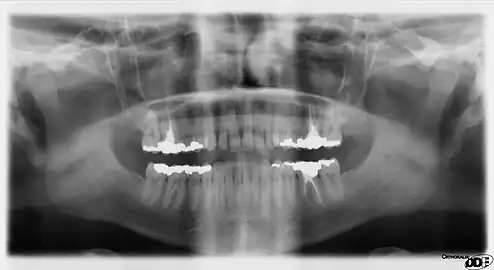

Panoramic radiograph

A dental panoramic radiograph, showing the maxilla and mandible, all the teeth including the "wisdom teeth," the frontal and maxillary sinuses, the nasal cavity and the temporomandibular joint and other near by head and neck anatomy. | |

A panoramic radiograph is a panoramic scanning dental X-ray of the upper and lower jaw. It shows a two-dimensional view of a half-circle from ear to ear. Panoramic radiography is a form of focal plane tomography; thus, images of multiple planes are taken to make up the composite panoramic image, where the maxilla and mandible are in the focal trough and the structures that are superficial and deep to the trough are blurred.